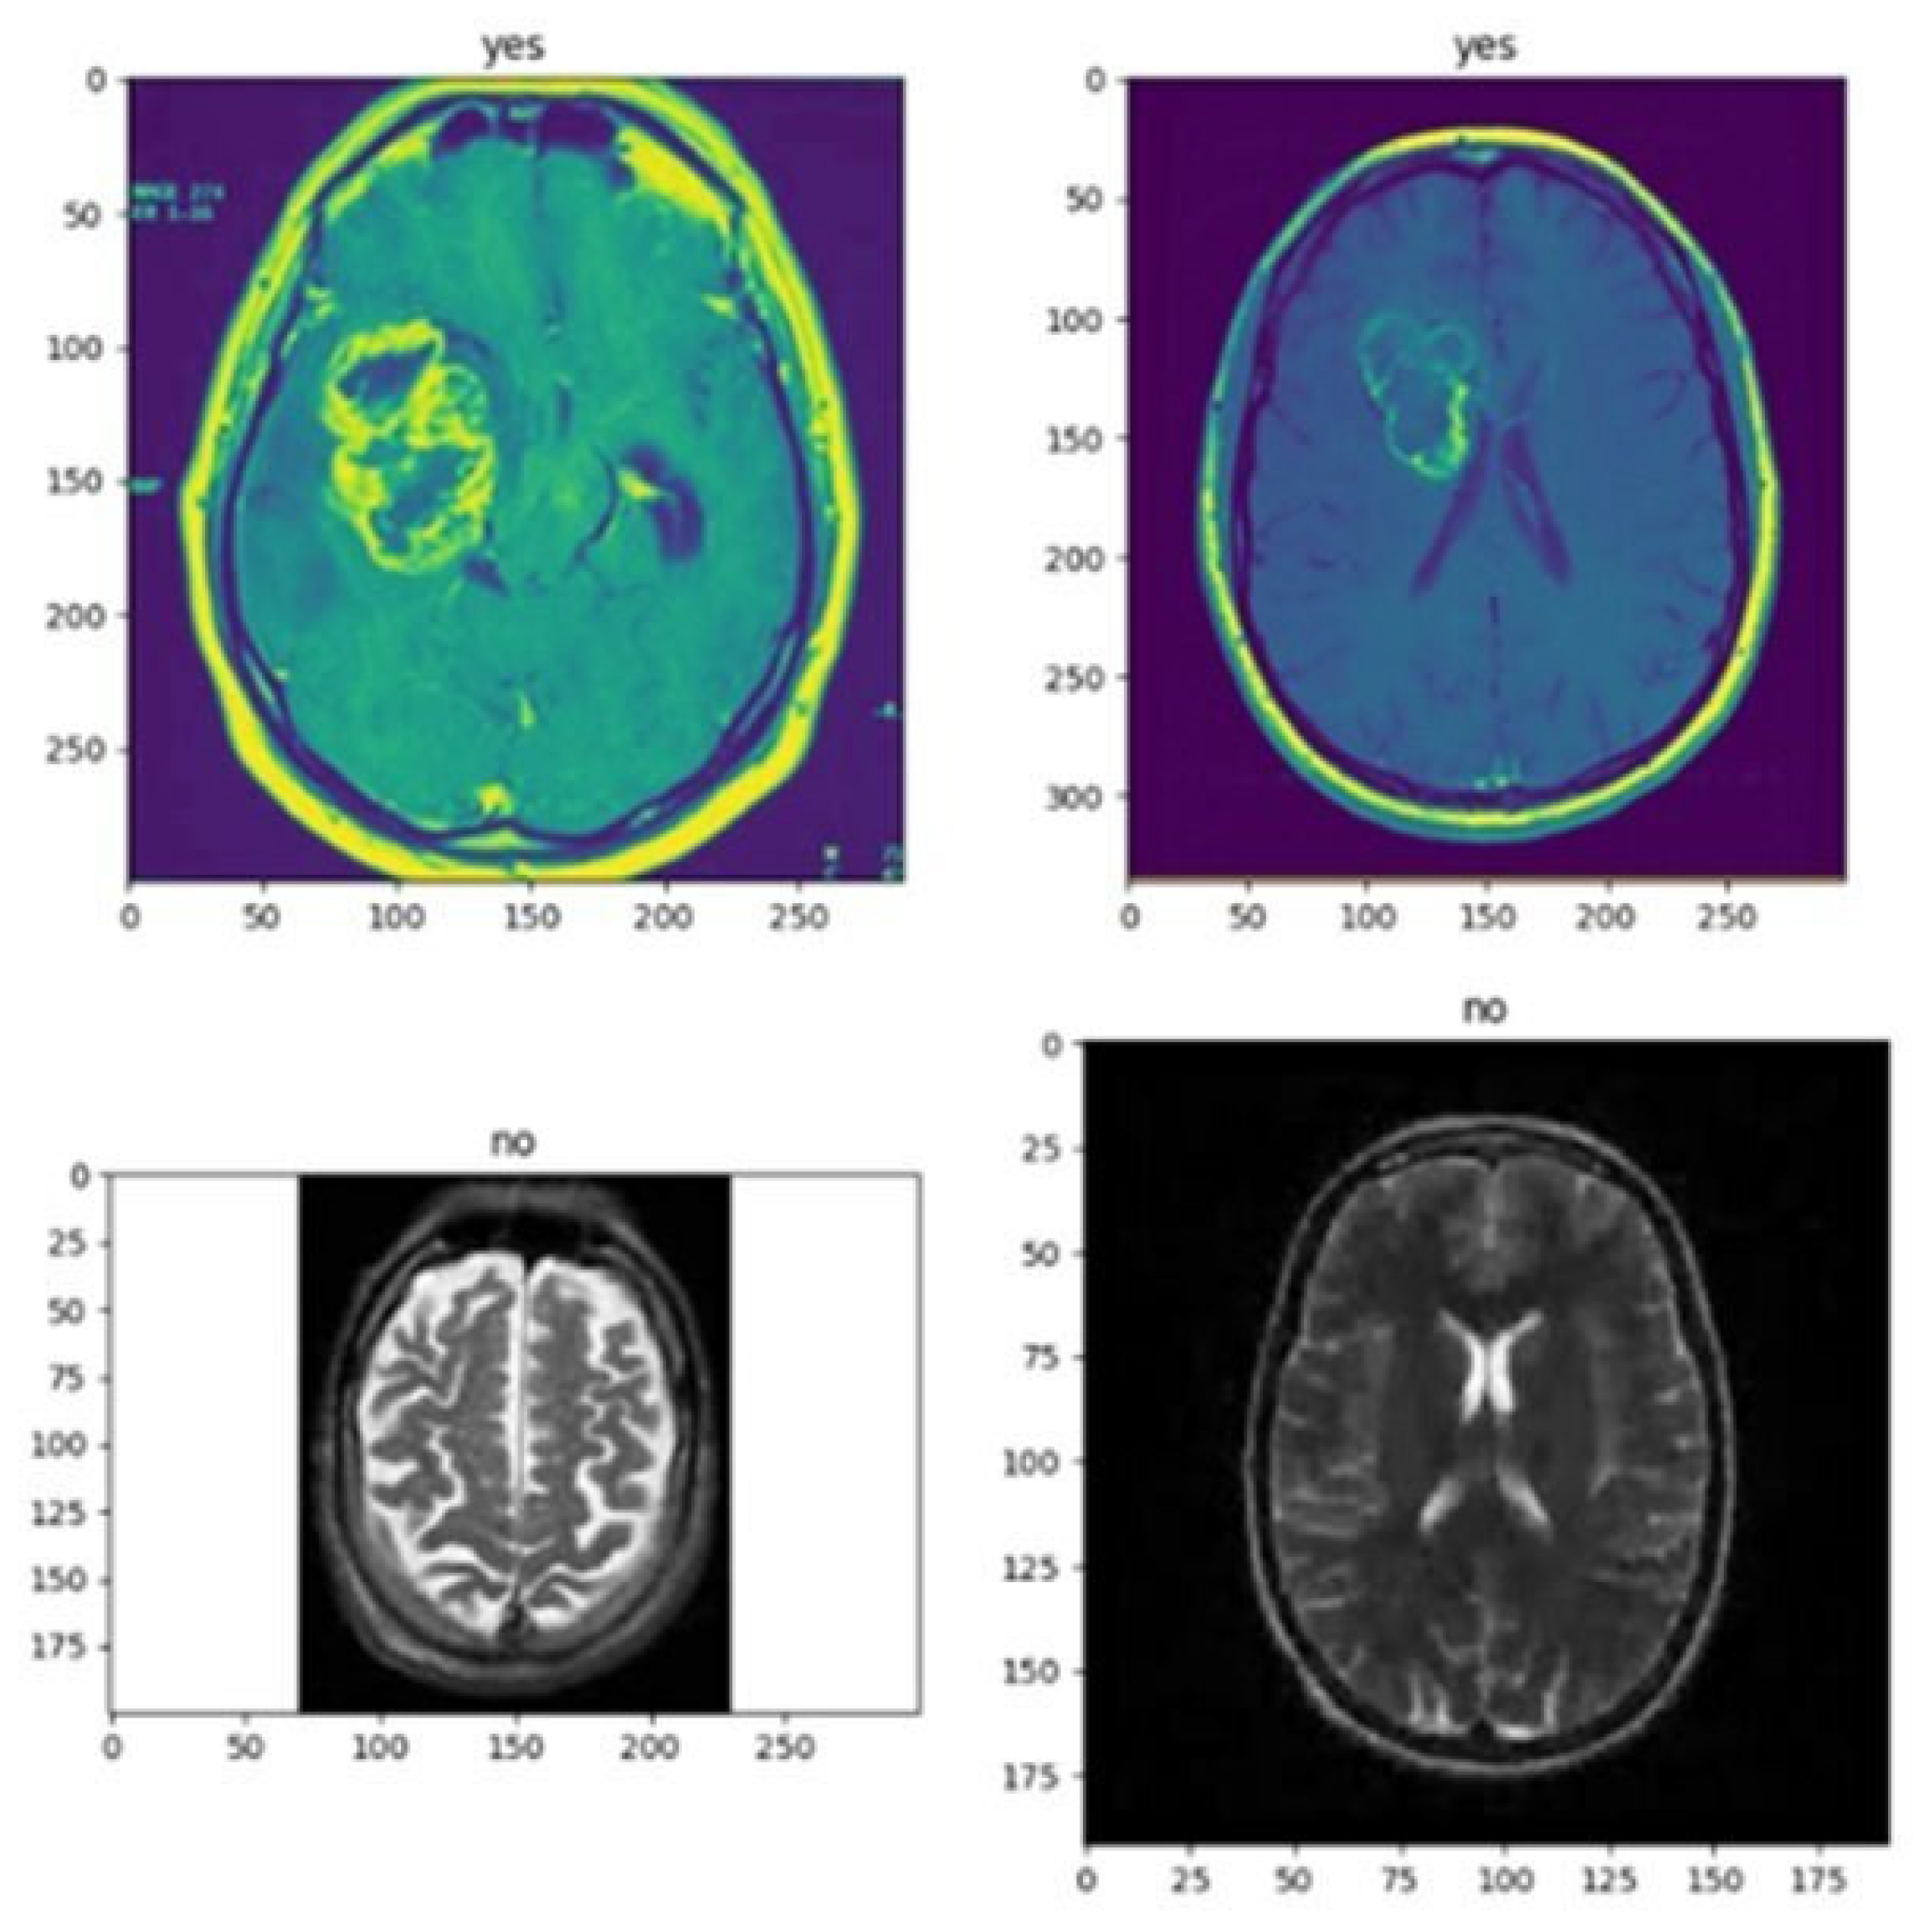

- Image Classification: In computer vision, classifying images is a frequent activity that entails labeling a picture according to its visual information. Image classification aims to create a model that can correctly recognize the objects or scenes that are seen in an image and give the image the appropriate label or labels.

- VGG16: With regard to picture classification, object detection, and segmentation, among other computer operations, this deep learning system has demonstrated state-of-the-art performance. Thirteen convolutional layers and three complete layers make up the sixteen layers of the VGG16 architecture. There are fixed-size 3 × 3 filters on convolution layers and fixed-size 2 × 2 filters on pooling layers. Each convolutional layer has twice as many filters as the previous layer, with the first layer having 64 filters. The output layer features a SoftMax function for categorization, and each layer includes 4096 units. The VGG16 architecture’s simplicity and consistency are among its key characteristics. Using fixed filters and filters in each layer, this model may be readily modified for various needs. Smaller-sized filters can also aid in maintaining performance.